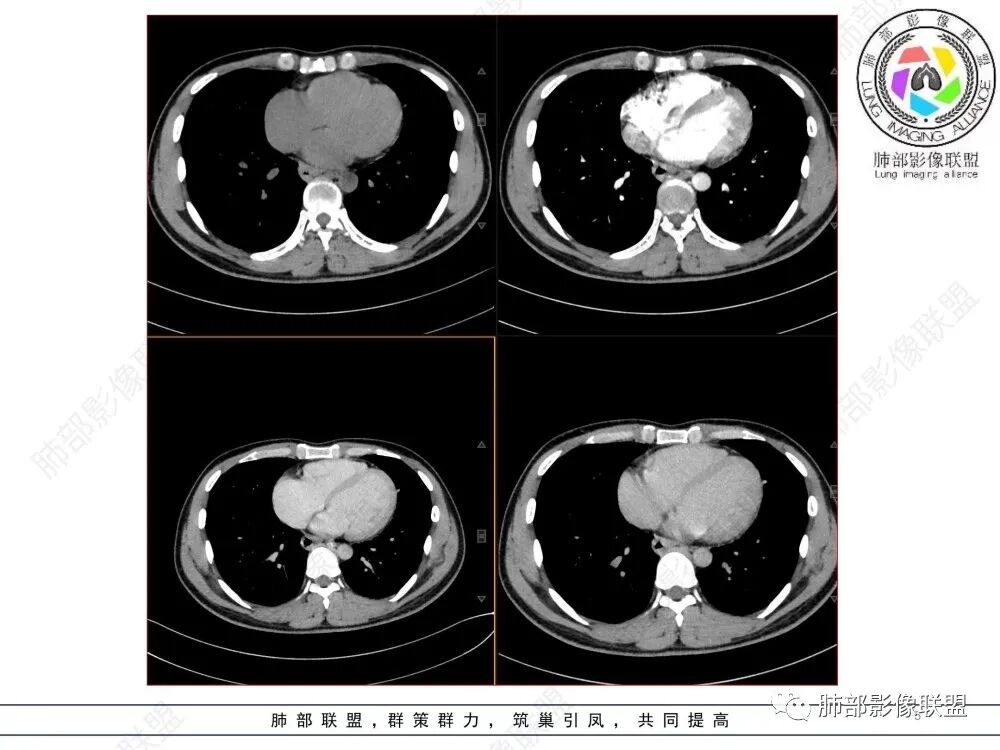

青年人,食管来源肿瘤性病变,平扫密度均质,病灶边缘分叶,食管部分僵硬,增强病灶轻中度强化,强化不愠不火,考虑恶性,淋巴瘤,鉴别食管平滑肌瘤,间质瘤。

食管下段近贲门处肿块,食道受压变窄,粘膜无破坏,轻度强化,T2等低信号,考虑平滑肌瘤?神经鞘瘤?鉴别间质瘤。

年轻男性,食管下段占位性病变长轴平行于食管,平扫密度尚均匀,增强轻度强化,MRI示T1、T2低信号,DWI低信号。考虑来源于食管,考虑平滑肌瘤或神经鞘瘤>间质瘤

定位后纵膈,这个位置,神经,淋巴,食管,轻微强化,T2低信号,弥散受限,考虑平滑肌瘤,鉴别神经原性。

平滑肌瘤(食管下段团块状肿块,环食管生长,分叶密度均匀,增强轻度强化。钡餐时食管受压移位,T1 T2 DWi低信号,病变来源于食管,考虑平滑肌瘤)

定位后纵膈,实性密度,增强轻度强化,T1等低信号T2低信号,弥散未受限。钡餐造影,食道及贲门管壁柔和,造影剂通过顺畅。考虑神经鞘瘤。鉴别食道平滑肌瘤。

后纵隔占位,质地均匀,信号中等,与食管关系密切,弧形受压,食管粘膜完整。考虑平滑肌瘤或孤立性纤维瘤。鉴别:神经源性肿瘤。

食管下段肿块,环壁生长,有分叶状,密度比较均匀,考虑食管粘膜下肌瘤。

食管下段后壁团块状肿块,管腔受压,密度均匀,增强轻度强化,食管受压移位,考虑平滑肌瘤,鉴别间质瘤。

食管下段肿块,管腔受压变窄,密度均匀,增强轻度延迟强化,考虑平滑肌瘤,鉴别间质瘤。

影像学特点:类纵隔区病变,沿食管生长,形态不规则,但边界清楚,内部信号/密度均匀,强化程度比较弱。

影像诊断思路:起源食管肿瘤(非黏膜起源,肌层起源),良性或低度恶性肿瘤可能性大,一般以神经鞘瘤、胃肠间质瘤及平滑肌瘤为主。食管神经鞘瘤强化明显均匀、以食管上段多见,周围常见炎性增大淋巴结,不太符合;胃肠间质瘤小的比较均匀,大的不均匀,但强化程度较高;影像上看这例病例比较符合平滑肌瘤。

食管平滑肌瘤是最常见的食管良性肿瘤,多见于男性,男女之比为2.6:1,高发年龄 30~60岁之间与食管癌相比,食管平滑肌瘤 的一个主要特点是病史相对较长,病情进展缓慢。病史最长者达10年余,平均 15.7个月,尽管病史较长,但大多数患者仍能进普食。食管平滑肌瘤的诊断一般比较容易,结合患者临床症状、食管造影及食管镜所见,一般均能得出正确诊断。食管造影主要为充盈缺损,病变与食管壁成锐角,粘膜线连续无破坏,管腔收缩扩张比较自如。钡餐造影敏感性高,但对食管壁间及食管周围情况难以判断。CT具有极高的密度分辨率,并且可以获得高质量的多平面重组图像,有利于食管壁间及食管周围情况的判断,表现为食管下段环绕管壁生长,偏心性或薄厚不均软组织密度肿块,密度均匀,内缘分叶状,管腔与正常食管壁构成不规则多角形扩张,增强动脉期无强化,多角度重建其病灶长轴与食管长轴不一致。由于食管壁在收缩状态下厚度约为5.6mm,扩张状态厚度不超过3mm,CT扫描时保持食管处于扩张状态可提高小病灶检出率。MR表现为T1加权等信号,T2加权稍高信号,可见高信号粘膜层,增强扫描轻度渐进性强化,密度均匀,无出血坏死。对于粘膜及周围脂肪间隙的判断具有明显优势。